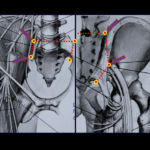

Diagnóstico e tratamento dos tumores músculo-esqueléticos, benignos e malignos primários dos ossos, lesões metastáticas e pseudo tumorais. Prevenção de fraturas em ossos osteoporóticos e patológicos.

Procedimentos cirúrgicos para o diagnóstico e tratamento das lesões neoplásicas do tecido músculo esquelético e reconstruções com próteses e soluções biológicas.

Tratamento ortopédico do aparelho locomotor e das lesões traumáticas. Osteossínteses das fraturas, Reconstruções biológicas ou com próteses de ombro, úmero, cotovelo, quadril, fêmur, joelho e tíbia.